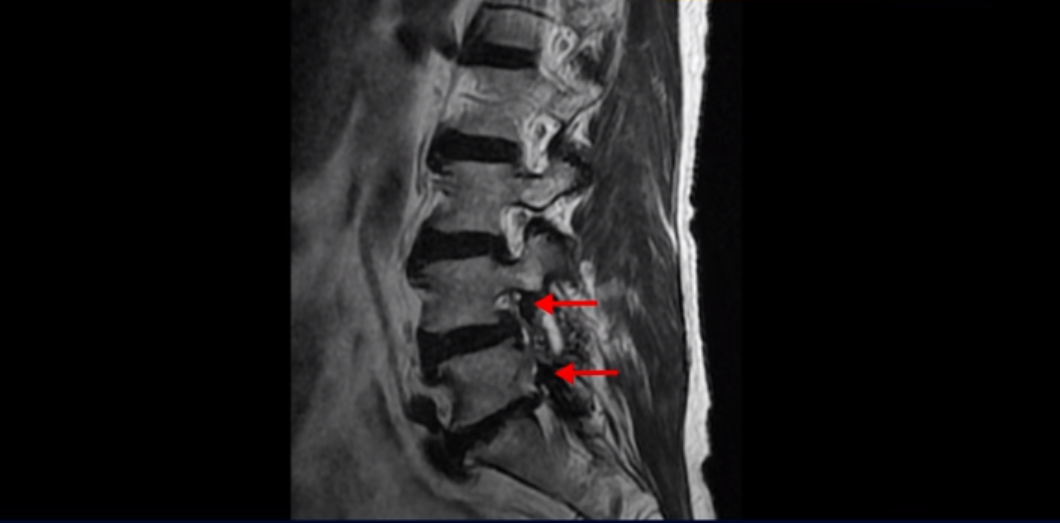

MRI를 보면 척추 여러 마디가 퇴행되어 있고

척추관도 좁아져 있고

특히 왼쪽 신경가지가 빠져나가는 4번 5번, 5번 1번 추간공들이 많이 좁아져 있습니다.

이분이 처음 아프게 된 건 작년 말입니다. 그런데 만일 이분이 아프기 전인 작년 초에 MRI를 찍었다면 지금 보시는 MRI와 많이 다를까요? 정답은 거의 차이가 없다입니다. 노화로 인해 신경 구멍이 좁아진 건 이미 오래 전에 벌어진 일입니다. 이렇게 신경 구멍이 좁아져 있는 채로 아무런 증상을 느끼지 않고 최소 5년에서 10년 이상 잘 산 것입니다. 이런 걸 잠복 협착이라고 합니다. MRI로 협착이 보이지만 아무런 증상이 없다는 뜻입니다.